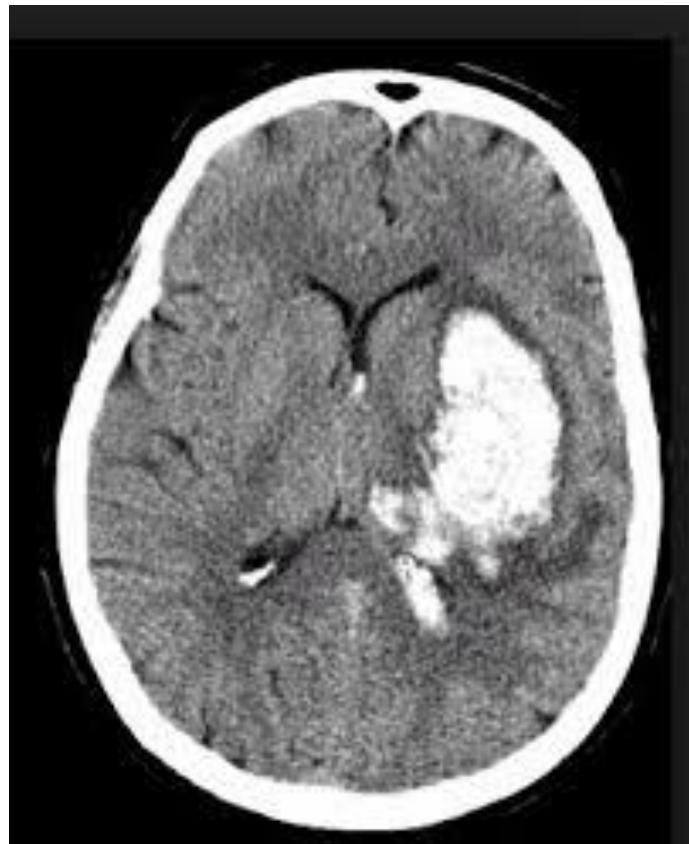

Ischemic Stroke

- Clinical Case: Face drop, weakness.

- Management: Perform CT to rule out hemorrhage before giving thrombolytics. - if hemorrhagic to OR STAT